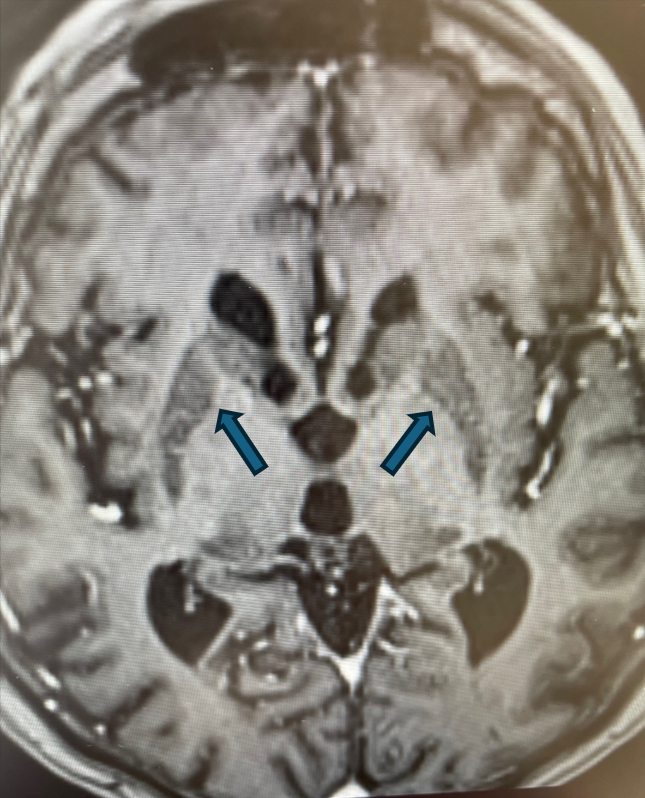

Rycina 4. Cechy akumulacji jonów żelaza w obrębie jąder zębatych móżdżku (T1).

rycinka